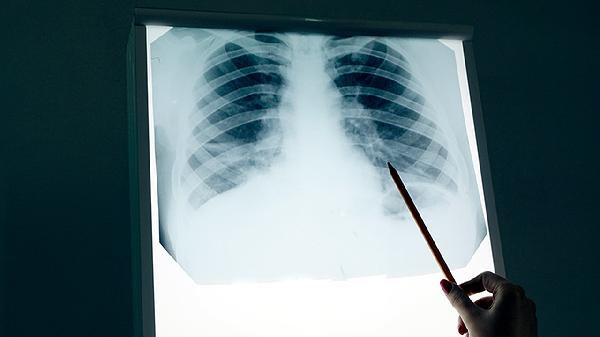

50岁以上人群发病率显著上升。建议每年做一次低剂量螺旋CT检查。